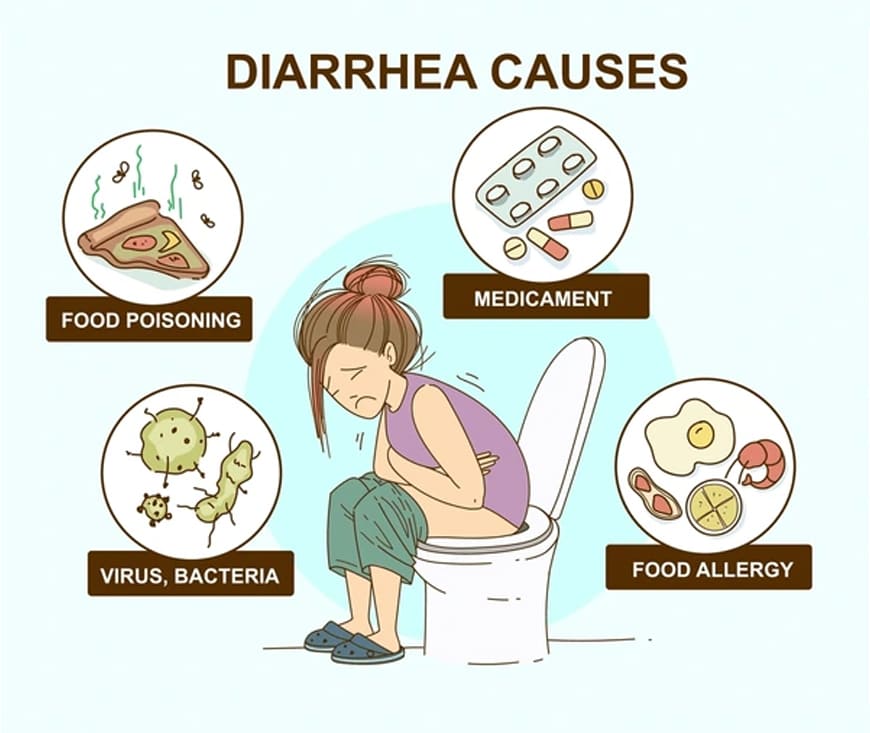

Diarrhea treatment focuses on hydration, as it can lead to dehydration. Oral rehydration solutions (ORS) help replenish lost fluids and electrolytes. Over-the-counter medications like loperamide can control symptoms, but should be used cautiously. A bland diet (e.g., BRAT—bananas, rice, applesauce, toast) is recommended. If diarrhea persists or is severe, consult a healthcare